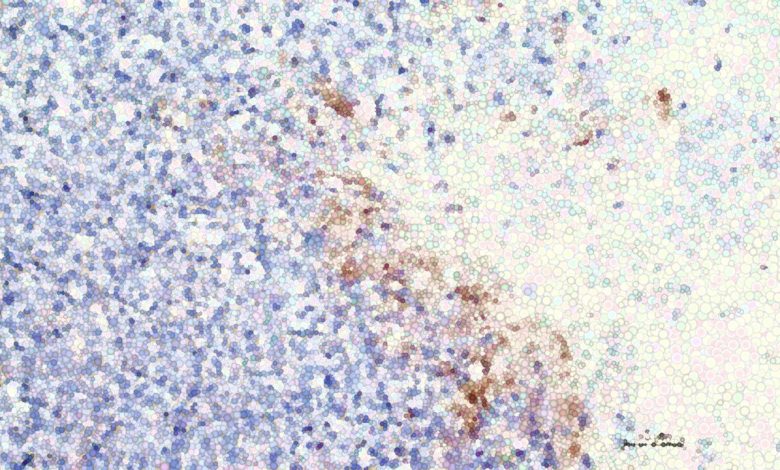

Imagem modificada digitalmente de células tumorais com células afetadas por CRISPR/Cas9 em marrom. Crédito: Instituto de Edição Genética